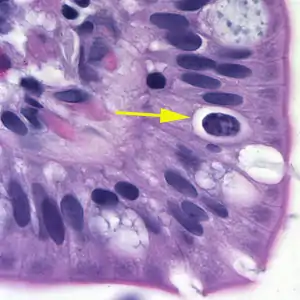

![]() | |

| Oocyst in epithelial cyst of mammalian host | |